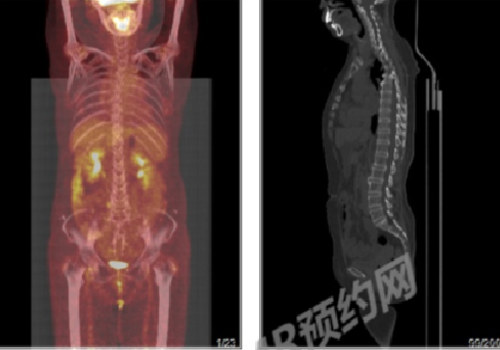

淋巴瘤治疗后复查,做PETCT检查案例-全国PETCT/MR检查预约网-癌症筛查-肿瘤复查-高端体检简要病史:患者2014年反复发热,未明确诊断,同时发现脾脏增大。2018.1右腰部肿物穿刺病理提示淋巴样细胞异常增生,肿瘤性病变不能除外,结合免疫组化考虑以T细胞性非霍奇金淋巴瘤首先考虑。后病理会诊考虑T淋巴样细胞弥漫浸润,考虑外周T细胞性非霍奇金淋巴瘤。2018.5反复发热,后行化疗8次,末次化疗结束时间为2019. 1。自述2018. 10外院PET评估病情好转。近2个月发现有下胸部皮下无痛性肿块,自觉变化不大。B超检查提示局部脂肪水肿。2020. 3发热一次,抗感染治疗后好转。1周前胸部CT未见明显异常。诊断结果:1.淋巴瘤治疗后,全身皮下脂肪间隙、肌肉及其间隙多发结节、骨髓不均匀FDG代谢异常增高,结合病史,考虑为淋巴瘤所致;腹盆腔内脂肪组织FDG代谢不均句轻度异常增高,结合病史,考虑为淋巴瘤浸润不除外。2.脾大。3.左肺下叶胸膜下斑片影,未见FDG代谢异常增高,考虑为炎性可能大,建议CT定期随访;双肺小结节,未见FDG代谢异常增高,建议随访;右肺少许纤维灶。4.脂肪肝;结肠炎;痔疮。5.椎体骨质增生。